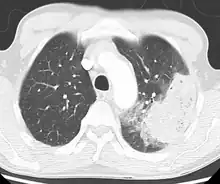

A chest X-ray showing a very prominent wedge-shape area of airspace consolidation in the right lung characteristic of acute bacterial lobar pneumonia

A black-and-white image shows the internal organs in cross-section as generated by CT. Where one would expect black on the left, one sees a whiter area with black sticks through it.

CT of the chest demonstrating right-side pneumonia (left side of the image)

A chest radiograph is frequently used in diagnosis.[20] In people with mild disease, imaging is needed only in those with potential complications, those not having improved with treatment, or those in which the cause is uncertain.[20][60] If a person is sufficiently sick to require hospitalization, a chest radiograph is recommended.[60] Findings do not always match the severity of disease and do not reliably separate between bacterial infection and viral infection.[20]

X-ray presentations of pneumonia may be classified as lobar pneumonia, bronchopneumonia, lobular pneumonia, and interstitial pneumonia.[66] Bacterial, community-acquired pneumonia classically show lung consolidation of one lung segmental lobe, which is known as lobar pneumonia.[34] However, findings may vary, and other patterns are common in other types of pneumonia.[34] Aspiration pneumonia may present with bilateral opacities primarily in the bases of the lungs and on the right side.[34] Radiographs of viral pneumonia may appear normal, appear hyper-inflated, have bilateral patchy areas, or present similar to bacterial pneumonia with lobar consolidation.[34] Radiologic findings may not be present in the early stages of the disease, especially in the presence of dehydration, or may be difficult to interpret in the obese or those with a history of lung disease.[21] Complications such as pleural effusion may also be found on chest radiographs. Laterolateral chest radiograph can increase the diagnostic accuracy of lung consolidation and pleural effusion.[33]

A CT scan can give additional information in indeterminate cases.[34] CT scans can also provide more details in those with an unclear chest radiograph (for example occult pneumonia in chronic obstructive pulmonary disease) and is able to exclude pulmonary embolism and fungal pneumonia and detecting lung abscess in those who are not responding to treatments.[33] However, CT scan is more expensive, has a higher dose of radiation, and cannot be done at bedside.[33]